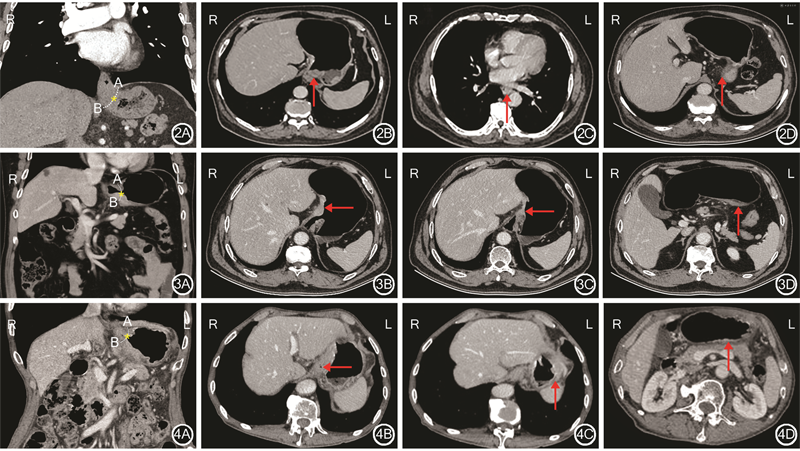

Siewert Ⅰ、Ⅱ、Ⅲ型患者实例展示见图2, 3, 4。

第一步,在门静脉期冠状位CT图像上找到角切迹A点,即食管和胃大弯解剖交界点,沿胃底大弯外壁连线逆时针向小弯侧延伸,跨过EGJ与胃体小弯的交点设为B点,两点之间的柔滑弧线即为食管胃交界线(α线)。之后通过定位线找到冠状位AB连线中点所对应的轴位层面,作为食管胃交界层面(“零点层面”)。

第二步,轴位图像公式法区分Siewert Ⅲ型与Siewert Ⅰ/Ⅱ型(区分食管或胃来源)。其中,肿瘤的上下缘层面均利用CT多平面定位进行确定:

上述公式中前半部分为肿瘤中心点的图像序号计算值,后半部分为食管交界线胃侧2 cm线的图像序号计算值。公式计算值即为肿瘤中心距食管胃交界线胃侧2 cm线的相对值。若计算值为正值则判定为Siewert Ⅲ型;若为负值,则为Siewert Ⅰ型或Ⅱ型。

第三步,轴位图像公式法判断肿瘤为Siewert Ⅰ型还是Ⅱ型:

若计算值为正值,则判定为Siewert Ⅱ型,若为负值,则为Siewert Ⅰ型。